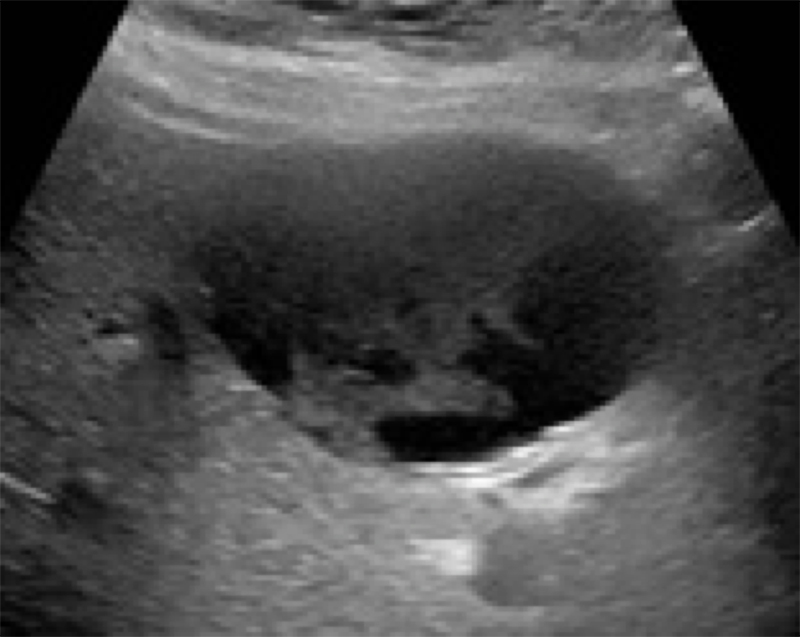

Figure 13. Cirrhotic liver with surrounding ascites. Note the surface nodularity of both anterior and posterior surfaces, parenchymal irregularity, shrunken liver size, and decrease in vasculature as compared to a normal liver.

Figure 14. Another example of a cirrhotic liver with surrounding ascites.